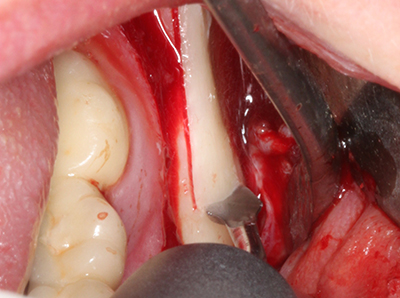

Aplicación: Preparación cerca del nervio

Como ya se ha mencionado, en el ámbito de la odontología conservadora también existen áreas en las que está indicada la cirugía piezoeléctrica. El uso de insertos de trabajo especiales facilita la representación del ápice radicular y, sobre todo en el área de los premolares inferiores y superiores, protege mejor los nervios y las mucosas del seno maxilar. En el caso de un cierre apical no estanco, los insertos de diamante acodados preparan de forma exacta y selectiva la cavidad de resección para el material de relleno retrógrado de la raíz. Gracias a la técnica de ultrasonidos, los insertos pueden presentar un diseño muy estilizado, lo que mejora la visión global y el tamaño de la cavidad de acceso. De este modo, en esta indicación, el uso de la cirugía por ultrasonidos se encuentra entre los métodos estándar para una apicectomía (Del Fabbro, Tsesis et al. 2010, Scarano, Artese et al. 2012).

Aplicación: Apicectomía

Si es preciso realizar intervenciones quirúrgicas en las que el hueso está en contacto directo con estructuras sensibles, como son los vasos sanguíneos o los nervios, los instrumentos rotativos presentan un enorme potencial de provocar lesiones iatrogénicas. Así, precisamente en la representación de nervios después de una lesión iatrogénica, o en el transcurso de la lateralización de un nervio para resecciones, reconstrucciones o incorporación de implantes, los equipos piezoeléctricos pueden resultar muy útiles para preparar la tapa ósea y retirar las partes de tejido duro cercanas al nervio (fig. 17-20). Por lo general, un ligero contacto del cordón nervioso con el inserto piezoeléctrico no tiene consecuencia alguna; ahora bien, un procedimiento poco cuidadoso con movimientos tipo sierra o piezas de trabajo sobre la base ósea aún existente puede provocar lesiones nerviosas temporales o incluso permanentes. Con todo, el riesgo de sufrir una lesión de este tipo se considera significativamente inferior que en los casos en los que se utilizan sierras y fresas (Pereira, Gealh et al. 2014).